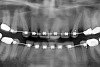

Figure 6a  A 50-year-old female concerned about appearance and bite. Jackscrew appliance was placed after 6 months of orthodontic alignment.

Figure 6a

Figure 6b  A 50-year-old female concerned about appearance and bite. Jackscrew appliance was placed after 6 months of orthodontic alignment (A to C).

Figure 6b

Figure 6c  A 50-year-old female concerned about appearance and bite. Jackscrew appliance was placed after 6 months of orthodontic alignment (A to C).

Figure 6c

Figure 6d  Figure 6d Patient was missing tooth No. 11 and had A-P and transverse maxillary deficiencies with anterior and left posterior crossbites. Bite was opened with glass ionomer cement. Single-tooth osteotomies were performed on teeth Nos. 6 and 12 and multiple-tooth osteotomies were completed on teeth Nos. 3 to 4, 7 to 10, and 13 to 14.

Figure 6d

Figure 6e  A 50-year-old female concerned about appearance and bite. Jackscrew appliance was placed after 6 months of orthodontic alignment (E). Jackscrews were activated 0.5 mm/day after 5-day latency period. Note pure translation of segments without tipping.

Figure 6e

Figure 6f  Jackscrews were activated 0.5 mm/day after 5-day latency period. Note pure translation of segments without tipping. Result 8 months postsurgery. Tooth No. 12 was converted to a canine, and an implant was placed in regenerate bone. Note amount of alveoloskeletal correction and increase in volume of maxillary arch. Also note in Figure 6c and Figure 6c the amount of protraction of maxillary anterior segments while anchorage was maintained in posterior segment. Restorative dentist: Michael E. Carter, DDS.

Figure 6f